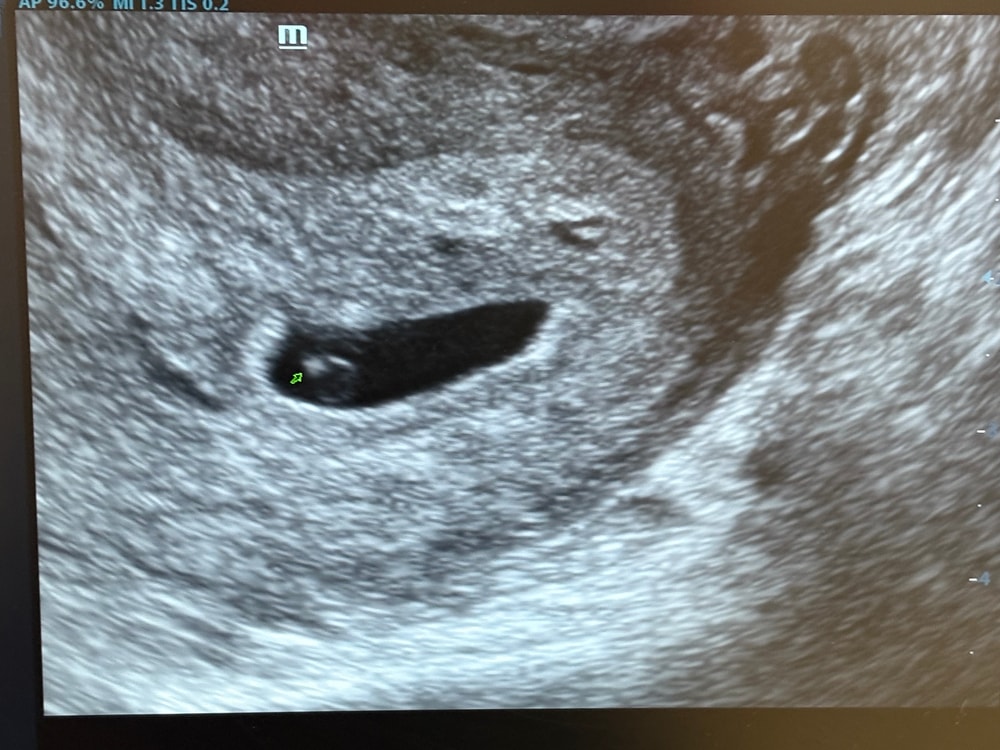

Девочки, помогите разобраться пожалуйста! Была сегодня на УЗИ, плодное яйцо 8 мм, эмбриончик около 1 мм, срок поставили 4 недели (гестационный срок, естественно). Сегодня вычитала, что уже должно быть сердцебиение, но врач сказала придти через пару недель, чтобы услышать сердечко. Я ничего не понимаю. Опять начиталась всего и снова волнуюсь. Помогите понять, пожалуйста, всё ли нормально. УЗИ прикладываю. По словам врача всё в норме. Но интернет говорит иначе.

У меня при плодном яйце 9 мм сердцебиение не обнаружили, переделала узи через неделю - уже было

Виктория Некрасова, ПЯ должно быть от 10мм, у меня как раз при таком ПЯ в эту беременность только пульсацию увидели и ктр у эмбриона 3,6мм был